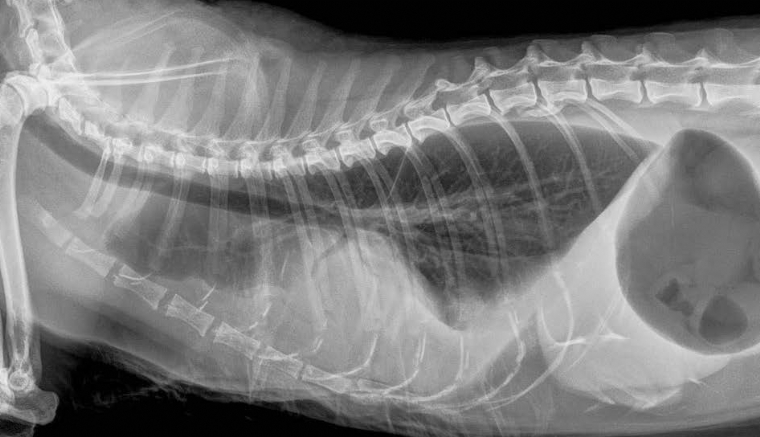

Le pyothorax chez le chien et le chat

Le pyothorax, aussi appelé empyème pleural, est défini par l'accumulation d'un exsudat purulent septique dans la cavité pleurale (CP). Un processus infectieux, bactérien dans la grande majorité des cas, provoque une augmentation de la perméabilité des ca...